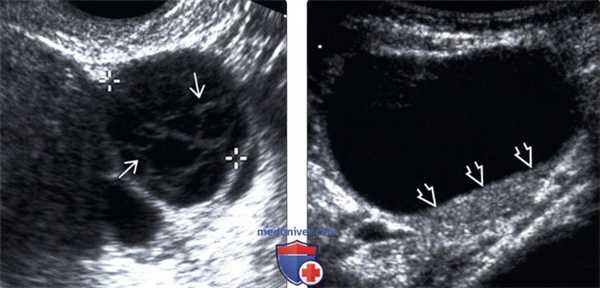

(Слева) КЖТ часто осложняется кровоизлиянием (отмечено калиперами). Геморрагическая КЖТ может иметь УЗ-картину в виде кружевного узора, а также тонкие перегородки, и обычно регрессирует спонтанно, что и визуализируется по данным трансвагинального УЗИ яичника в В-режиме.

(Справа) В этом случае КЖТ, тщательная оценка задней стенки кисты выявляет наличие уровня «жидкость-взвесь». Визуальная картина соответствует регрессирующей геморрагической кисте.